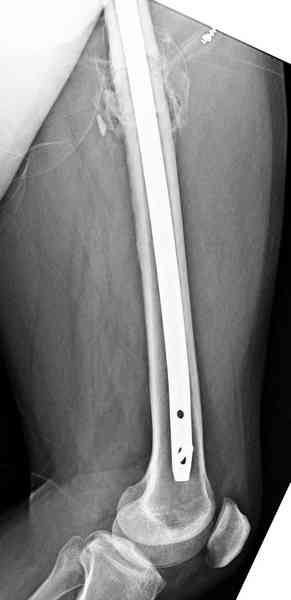

Здесь представлены снимки больного 65 лет, поступившего с диагнозом перелом

бедра после автоаварии.

В первый же день произведено антеградное штифтованием DePuy Trochanteric Nail.

и проведены шурурпы через и спереди штифта без удаления.

Послеоперационные снимки